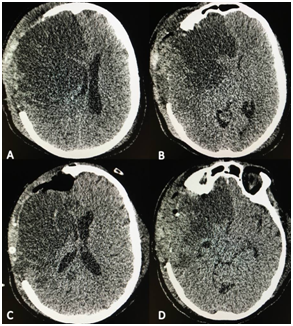

On the third day, the patient started with ICP records higher than 20 mmHg that were refractory to medical treatment. Brain CT showed a frank increase of the hypodense area in the left MCA territory with mass effect increase, given by compression of the ventricular system and a 8 millimeter midline deviation. Infarcted left temporal lobe was resected with the same limits as in the previous cases. The control CT showed improvement of the mass effect (Figure 2). After two months of evolution, the patient was awake, fulfills orders and presented anomies in the naming of objects that allow him to communicate with difficulty. He continued with right hemiplegia. We managed to retired the tracheotomy and gastrostomy and remained with rehabilitation (mRS 5).

Figure 2 A) CT scan before the temporal lobectomy. The stroke is observed as a hypodense area which produced compression in the ventricular system and midline shift. B & C The CT scan after the temporal lobectomy showed absence of complications and an improvement in the mass effect with restoration of the midline.